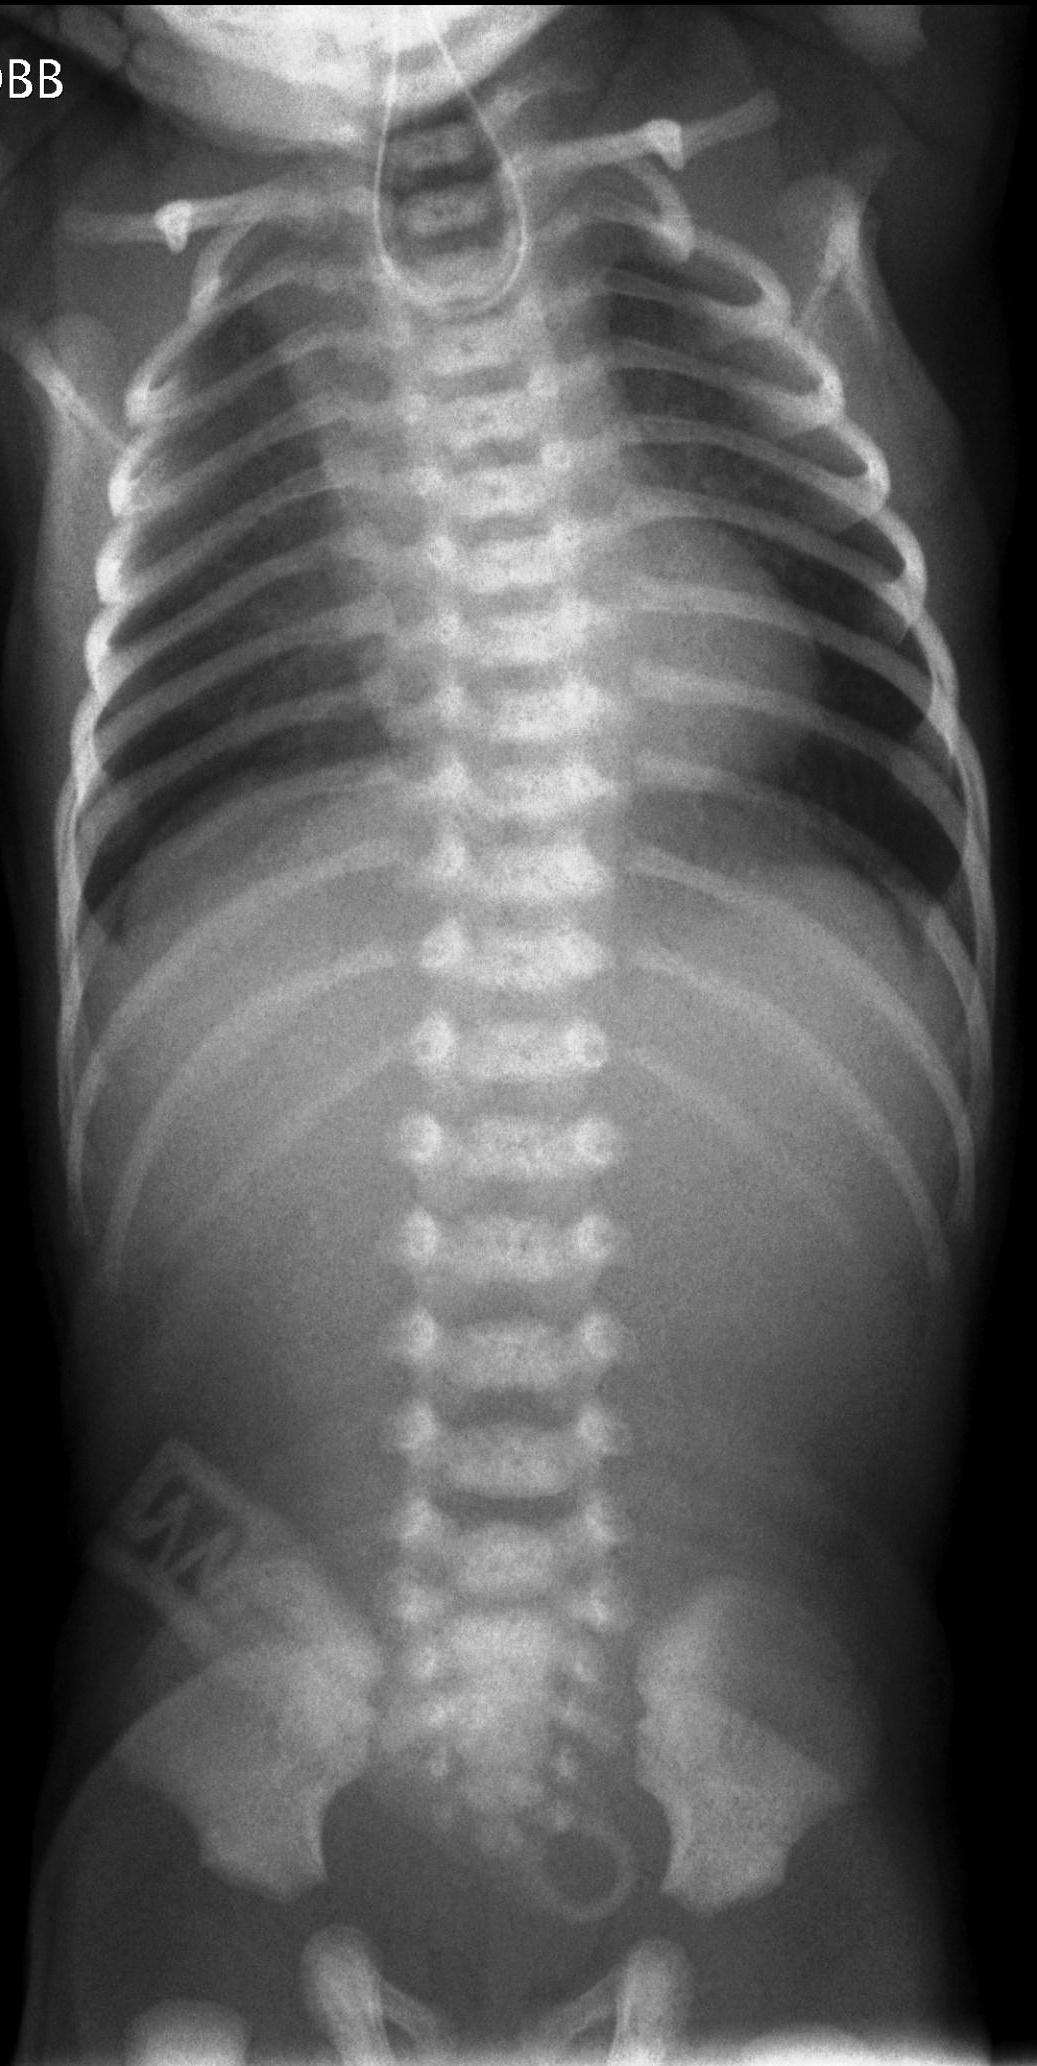

X-ray examination: an X-ray absorbent tube is visible in the obstructed diverticula of the esophagus. In cases of a lower fistula, the intestines are aerated, the accompanying costal and vertebral abnormalities can also be observed.

Esophageal atresia: is commonly located at the level of the upper/middle esophageal border and is sometimes associated with tracheo-esophageal fistulas. Newborns are unable to swallow their saliva and the diagnostic tube gets stuck in the esophagus. The most common form is atresia with a lower fistula. In 50% of the cases other abnormalities are present; as part of the so called VACTERL syndrome (vertebral, anal, cardiac, tracheo-esophageal fistula, renal and limb) various additional abnormalities can be observed.

10.The tube inserted in the esophagus turns back in the height of the 4th Thoracic vertebra, the intestines are filled with gas. Esophagus atresia with lower fistula.